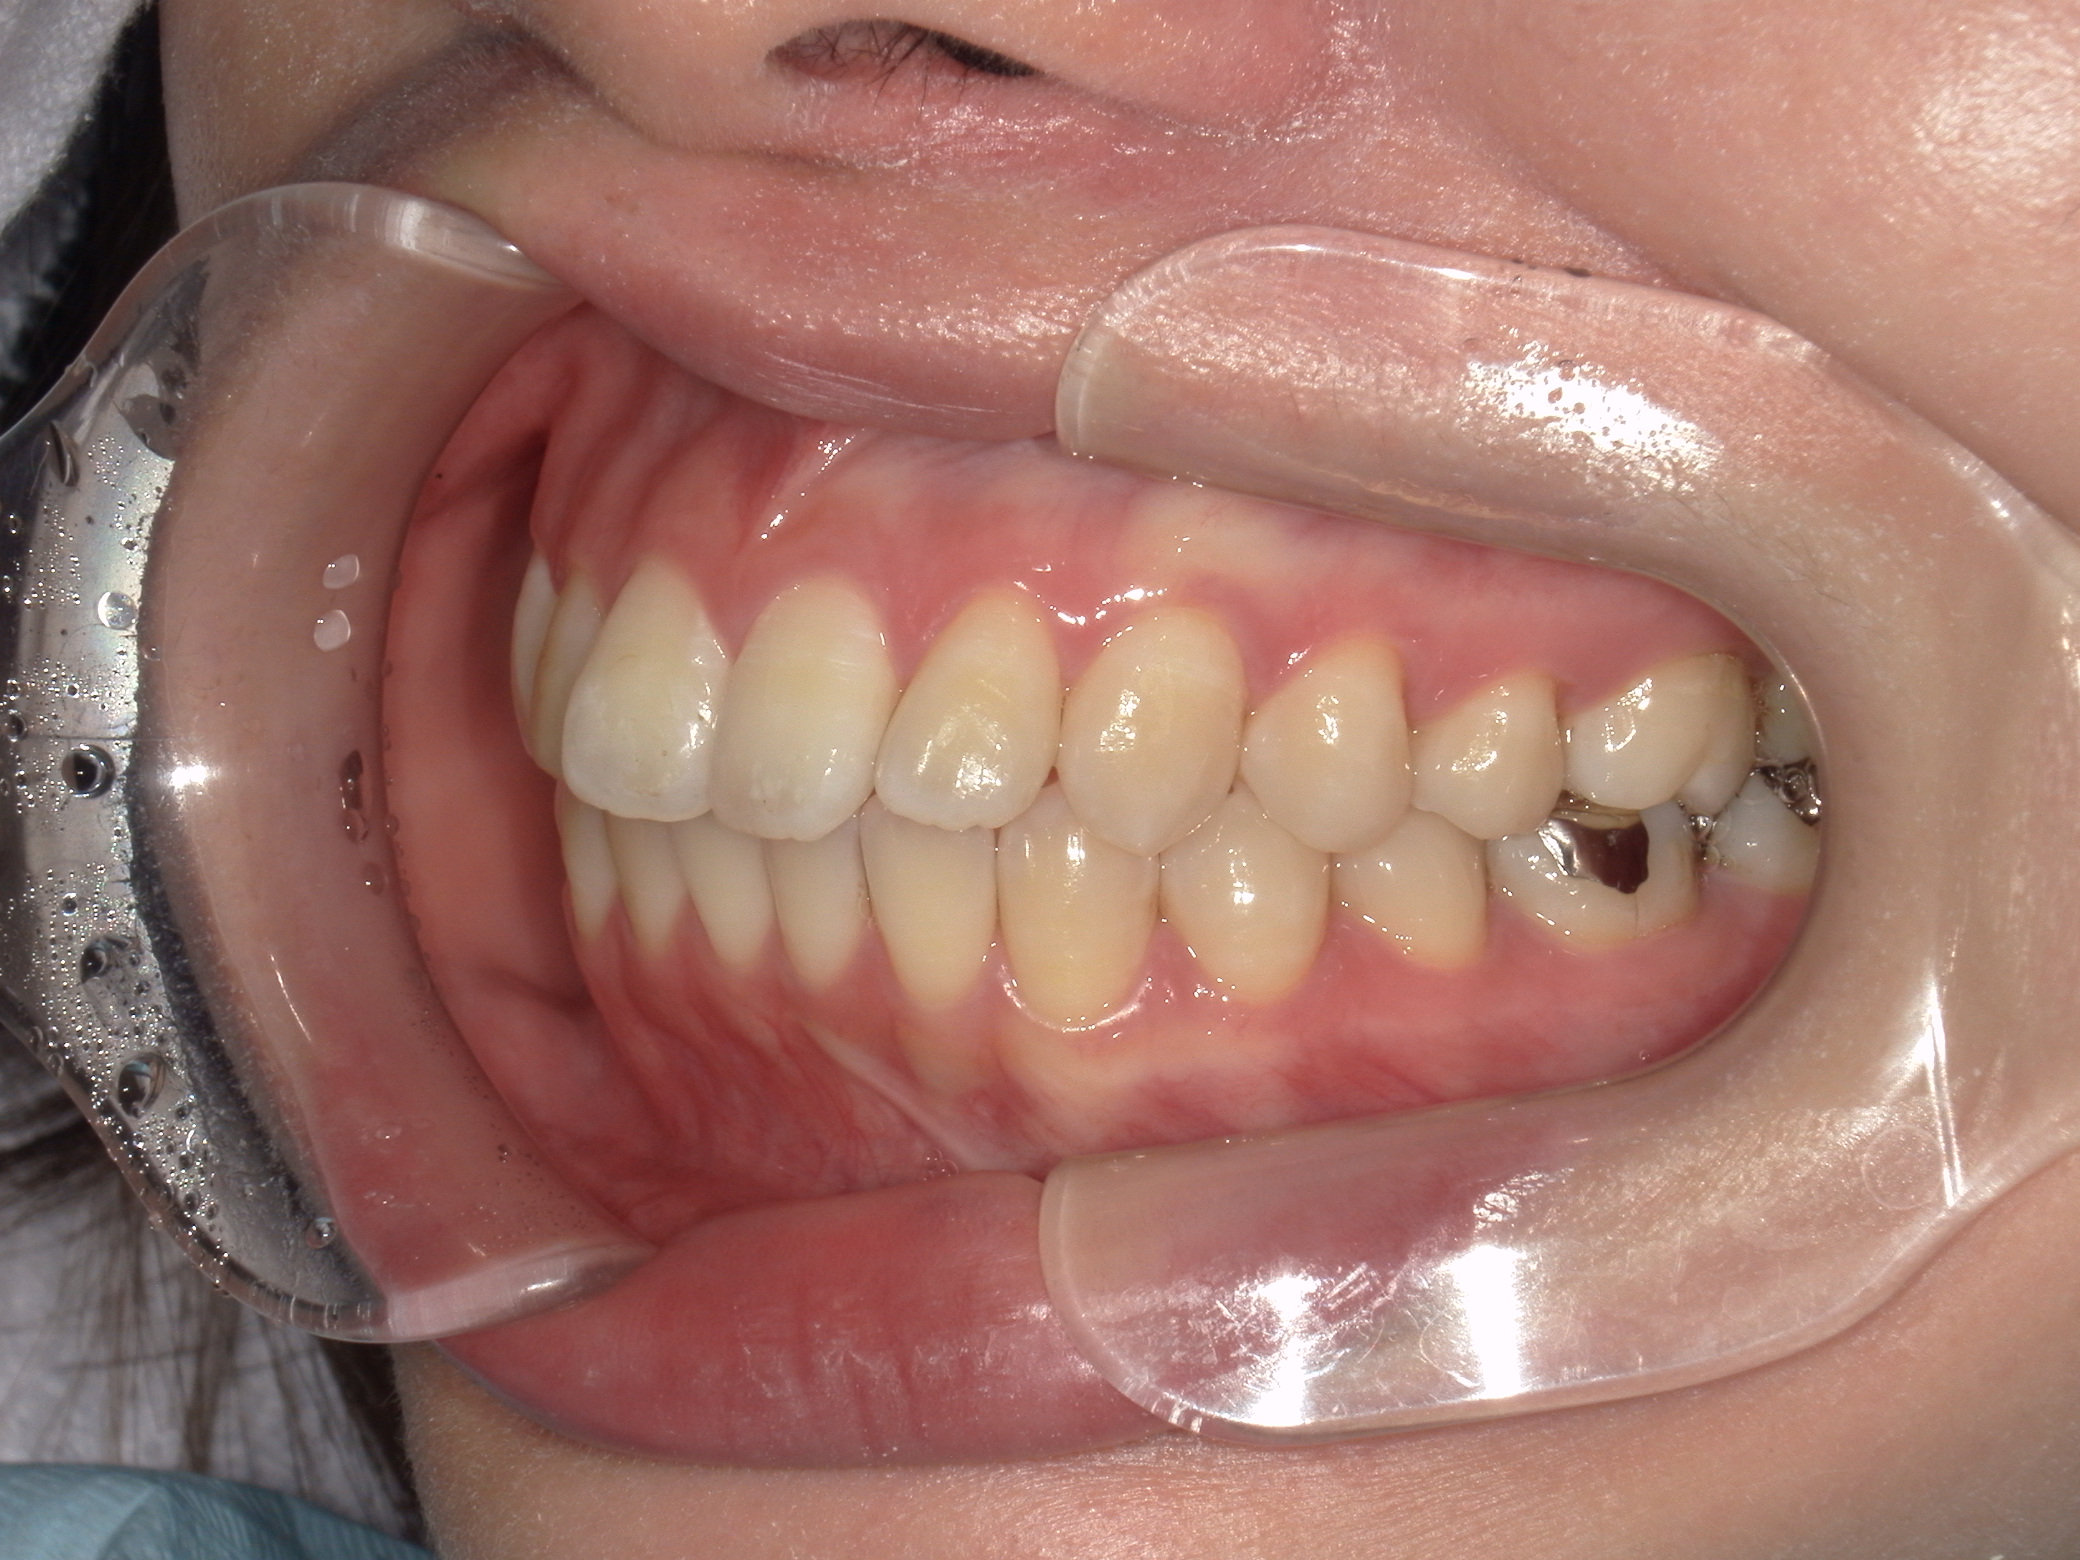

治療後、口元の突出感の改善、咬合関係は維持することができた。

上下小臼歯抜歯により突出感を改善する計画を立てた。確立した咬合を崩さないように治療を進める事を目標とした。